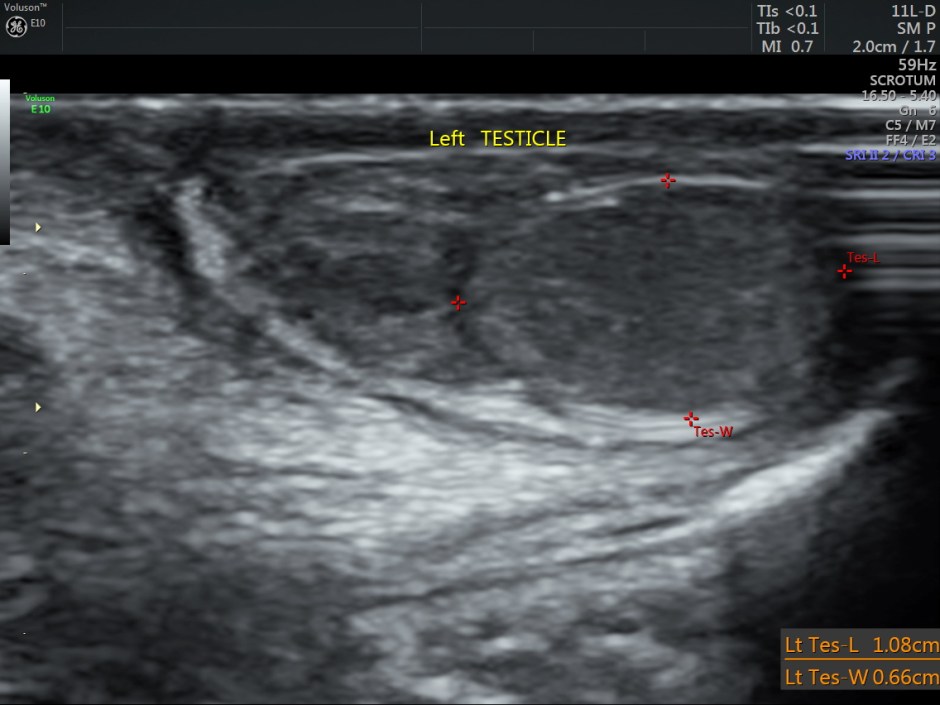

Ultrasound showed the two testicles in the scrotal sac and a cystic swelling above the right testis, distinctly separate from the same. Both the testicles appeared to have normal echotexture.